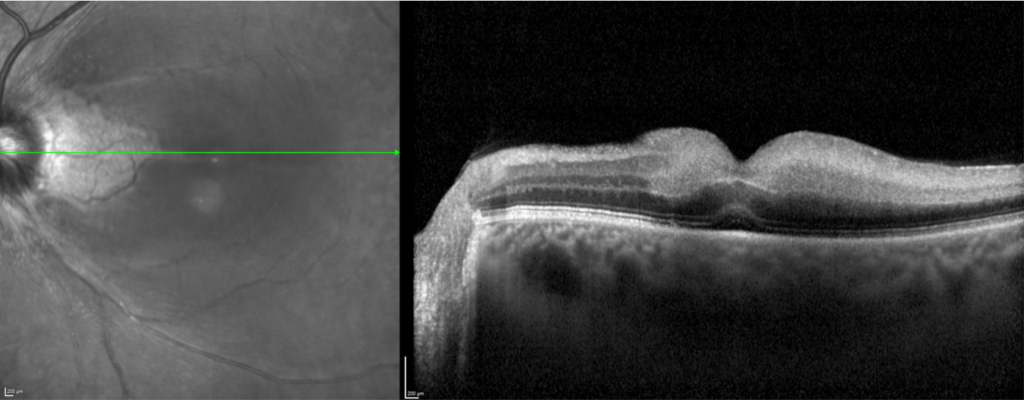

Coupe en OCT montrant un œdème maculaire avec infiltration des segments internes, des photo récepteurs et un décollement de l’épithélium pigmentaire.

L’examen doit être réalisé en urgence. Une mesure de l’acuité visuelle par l’orthoptiste est réalisée, suivie de l’instillation de collyres dans les deux yeux. La dilatation des pupilles permet à l’ophtalmologiste d’explorer le fond d’œil et de réaliser une angiographie rétinienne à la fluorescéine. Un OCT maculaire complète le bilan et met en évidence la présence d’œdème maculaire.